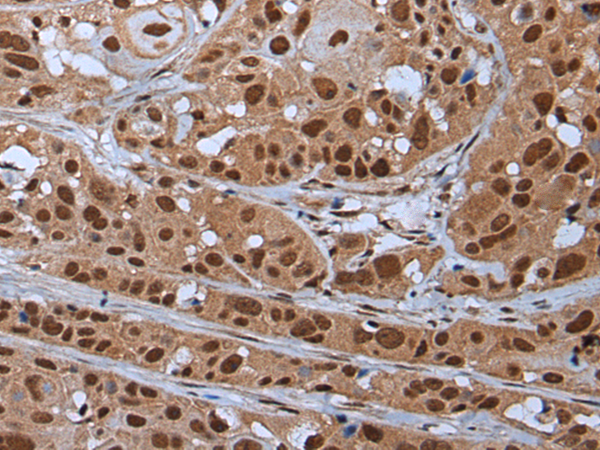

分类: 科研抗体货号: P05889别名: SAR1; p195; HUMORFA01应用: WB,IHC反应种属: Human, Mouse